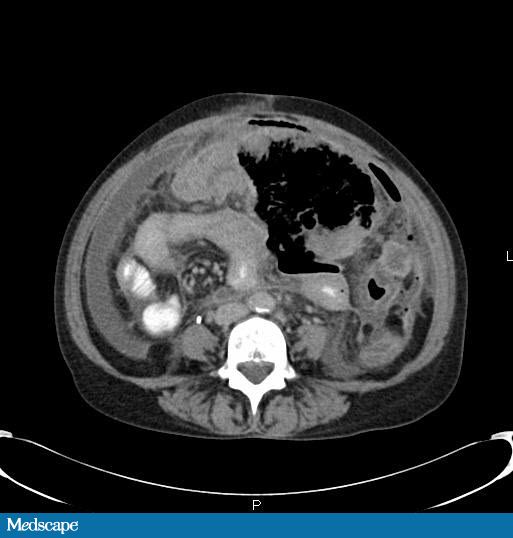

Ct scan of the abdomen for abdominal pain is one of the most common reasons for ordering a ct scan. This abdominal ct scan shows tumor masses (malignant lymphomas) in the area behind the peritoneal cavity (retroperitoneal space). Computed tomography (ct) of the abdomen and pelvis is a diagnostic imaging test.